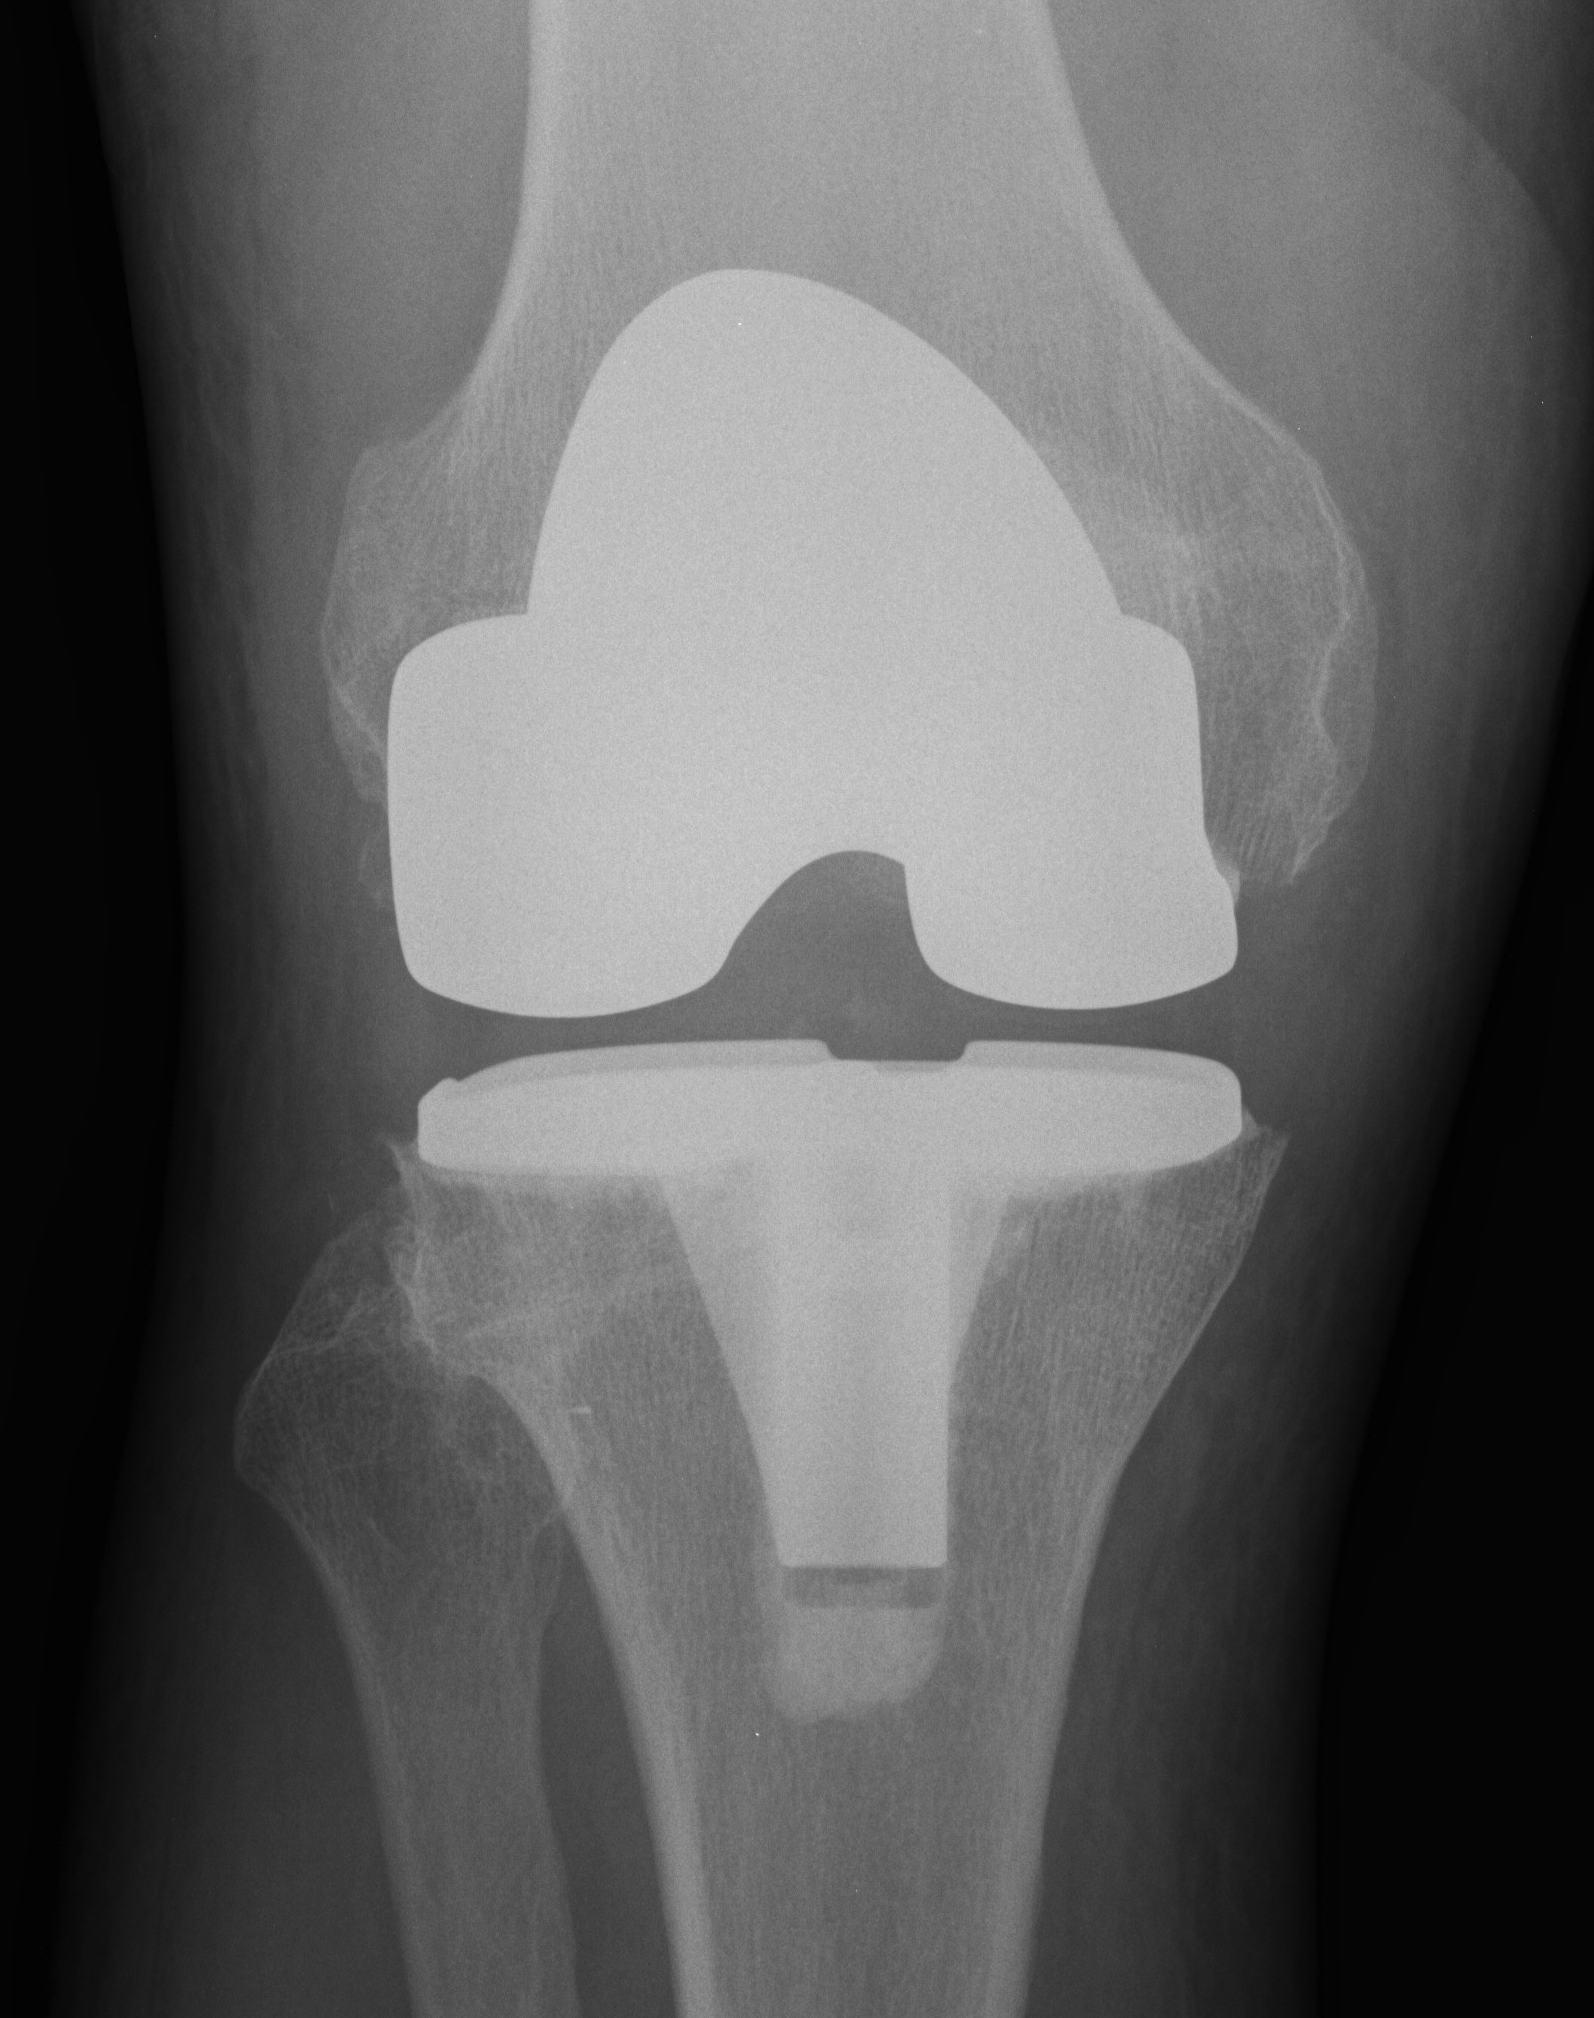

Soft tissue Balancing

Valgus knee alignment

- need appropriate releases

- restoring the tibial slope

- difficulty with flexion / extension balancing

- may need higher constraint